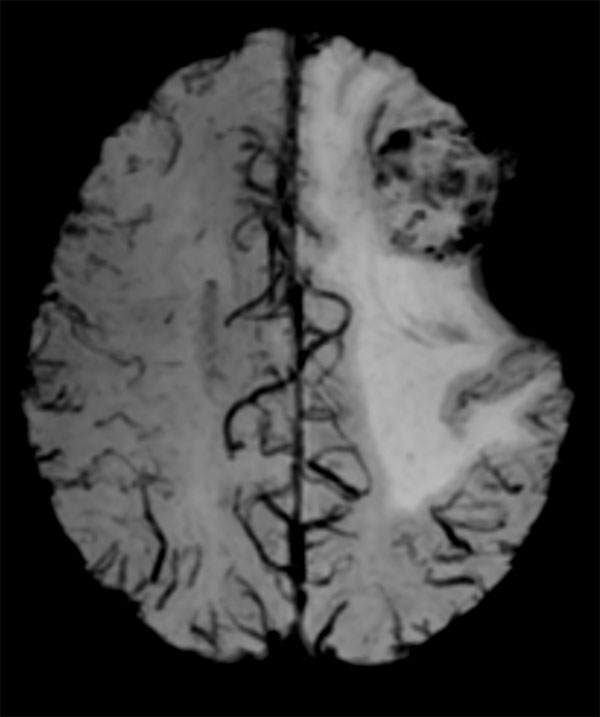

Axial Venous BOLD